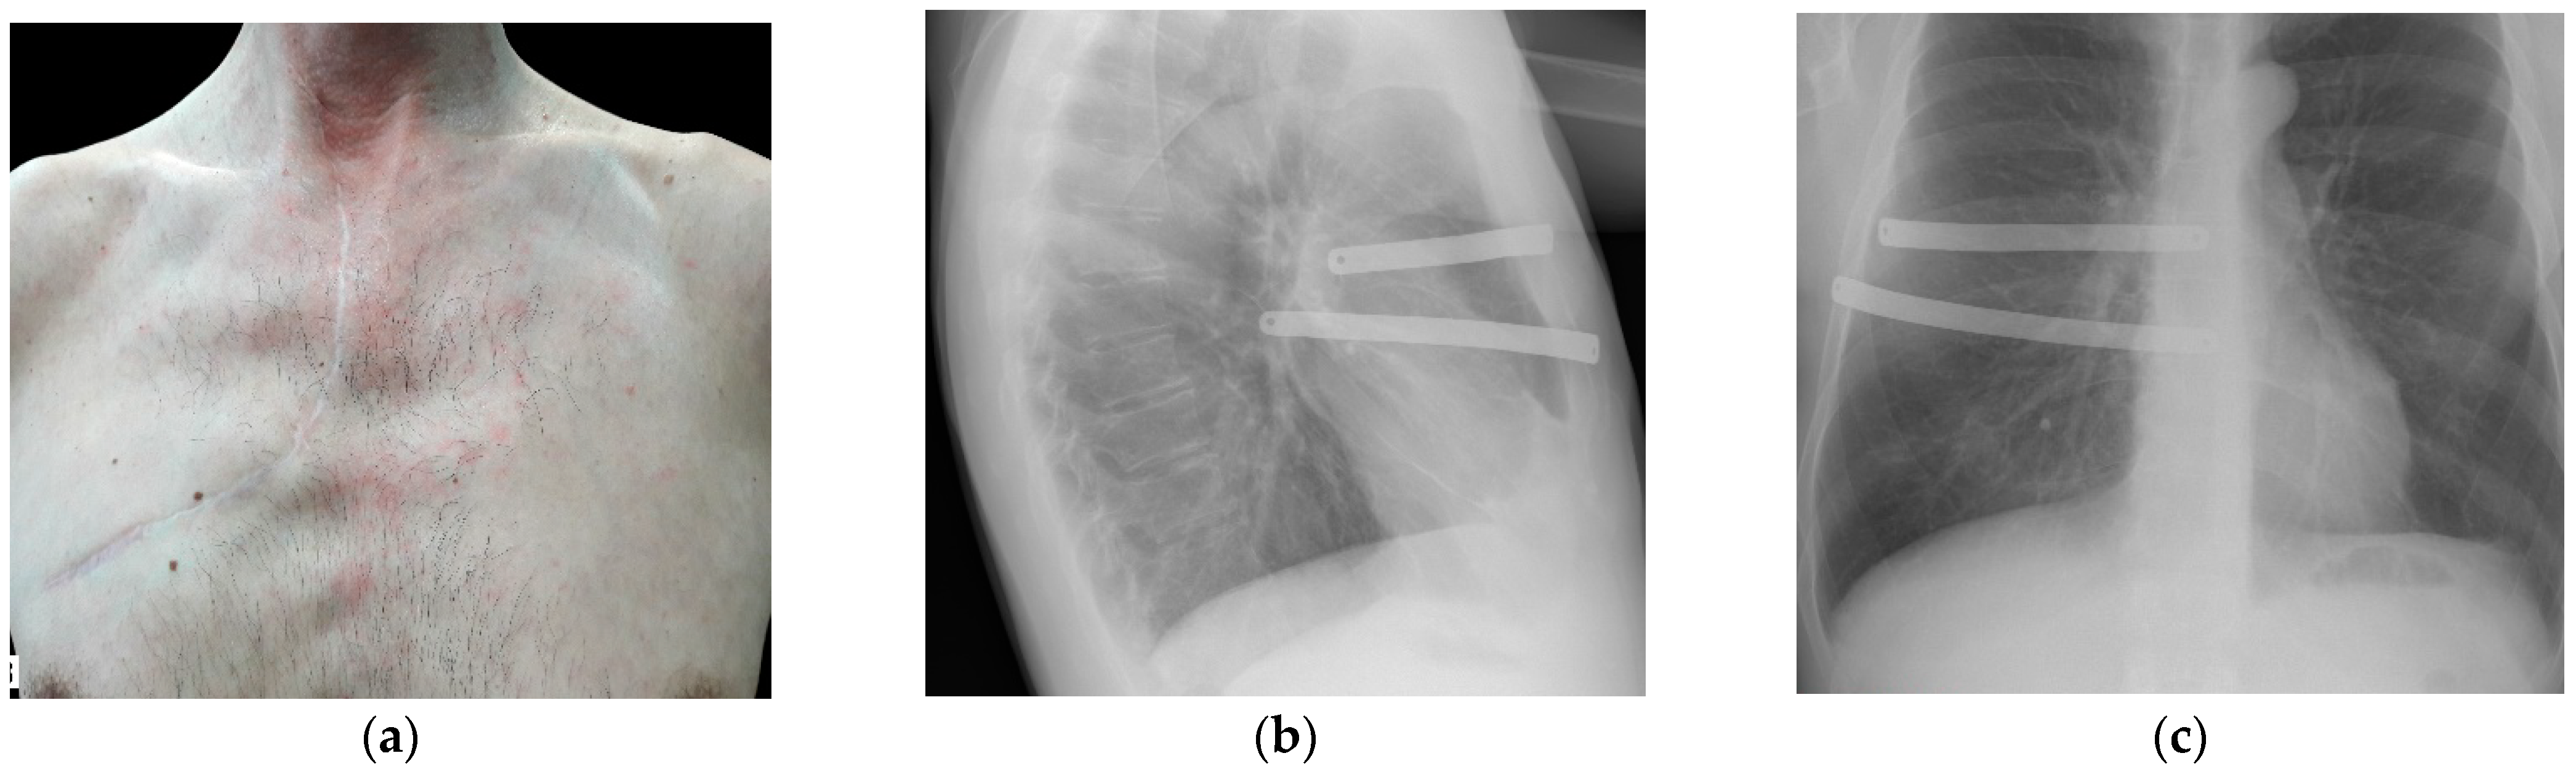

2. Materials and Methods

3. Results and Discussion